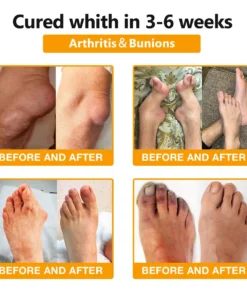

The ArthroFree™ Bee Venom Pain-Relief Bone Healing Cream is celebrated for its efficacy in addressing a wide array of orthopedic conditions. These include osteoarthritis, rheumatoid arthritis, bursitis, tendinitis, osteoporosis, gout, carpal tunnel syndrome, ligament sprains and strains, bunion deformities, and tennis elbow.